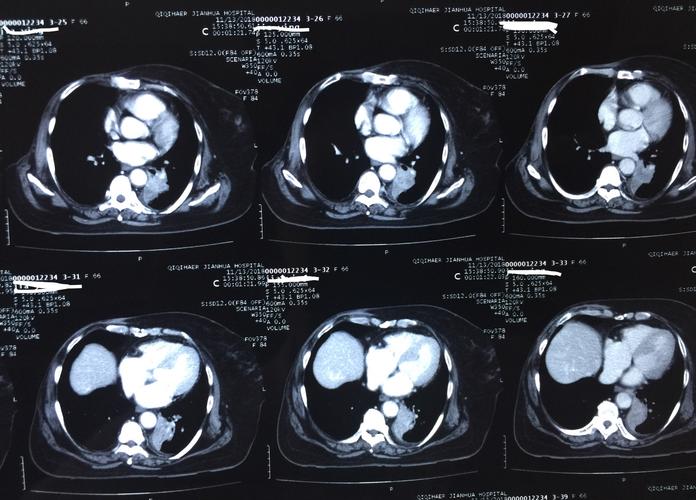

术前肺部增强ct片

癌症ct片子图片

肺癌ct图片

癌症ct

肺部ct图片

肺部肿瘤ct图片